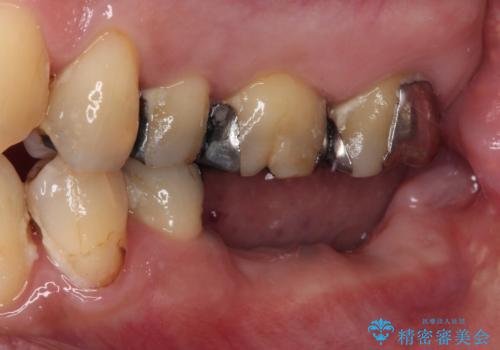

- 抜歯をしたものの、インプラントにするか入れ歯にするか悩んでいるうちに2年以上経過してしまったとのことで来院された患者様です。

自分の歯のように噛めるようにしたいとのことで、インプラントによる欠損補綴治療を行うこととしました。